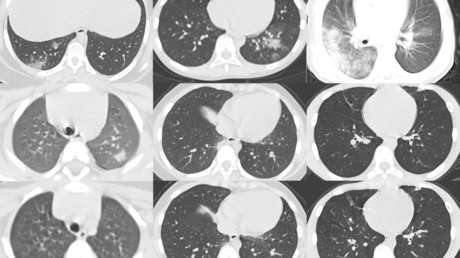

Los resultados de su investigación, publicados en la revista American Journal of Roentgenology, citan un estudio que reveló, gracias a tomografías computarizadas de tórax, que casi dos tercios de los 20 niños menores de 14 años con el covid-19 observados en Wuhan (China) presentaban opacidad en vidrio esmerilado, un indicativo de que existe una inflamación generalizada.

Además, la mitad de los pacientes mostraban la condición conocida como 'el signo del halo', que hace que la inflamación rodee una masa conocida como consolidación, que dificulta la respiración debido a la presencia en los alvéolos pulmonares de sustancias como líquido o infección. La consolidación es un síntoma de neumonía y puede causar problemas respiratorios porque el aire inhalado no puede atravesar la masa obstructora.